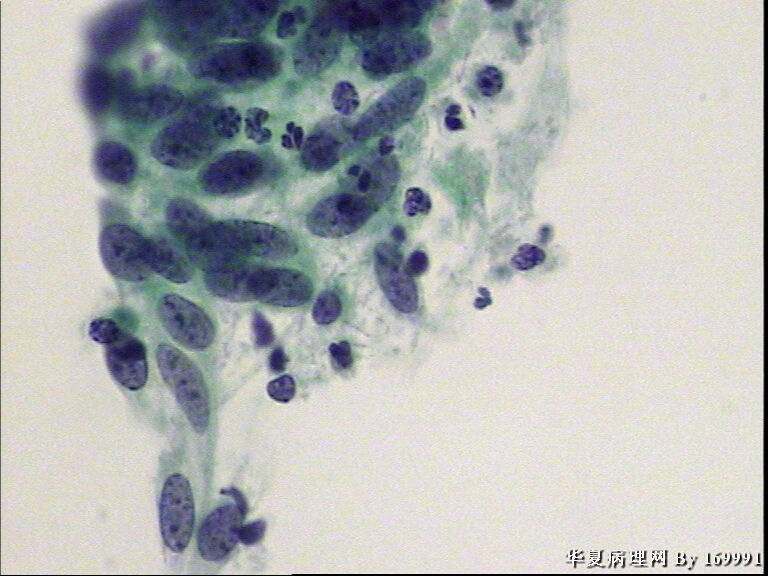

宫颈液基,患者60岁,宫颈轻糜,鳞癌?

• 宫颈液基,患者60岁,宫颈轻糜,鳞癌?图2

图2

HSIL累及腺体

是的,此例没有直接报癌,最后报了HSIL,不除外SCC.建议活检。

宫颈活检结果:宫颈原位癌,累腺。